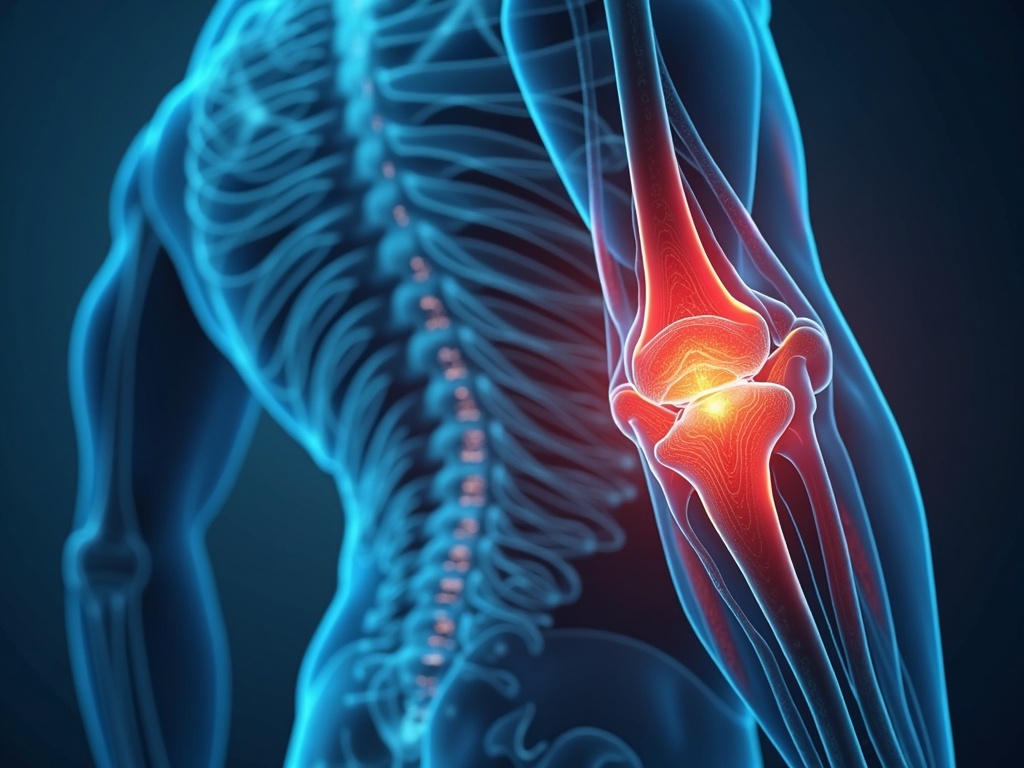

That nagging ache in your knee after a round of golf? The stiffness in your shoulders that makes reaching for the top shelf a daily trial? As men, we often push through physical discomfort, attributing it to ‘getting older' or ‘overdoing it’ at the gym. But chronic joint pain doesn't have to be a life sentence. While popping pills might seem like the easy answer, more and more men are discovering the potent, natural relief offered by acupuncture. This ancient practice could be the key to unlocking lasting joint pain relief and getting back to the activities you love.

- Osteoarthritis: This degenerative joint disease affects millions, particularly as we age. Cartilage, the cushion between bones, breaks down, leading to pain, stiffness, and reduced range of motion.

- Bursitis and Tendinitis: Inflammation of the bursae (fluid-filled sacs cushioning joints) or tendons (connecting muscle to bone), often due to overuse or repetitive motions.